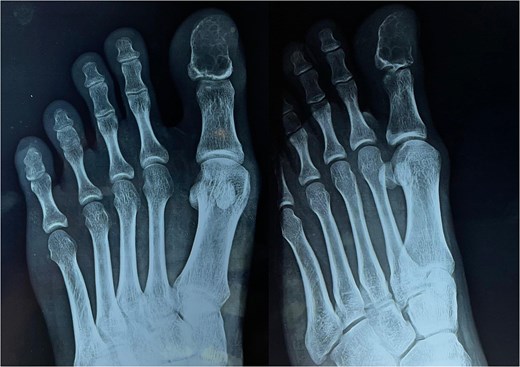

Guided biopsy was taken and sent for histopathological examination but was inconclusive. A chondroblastoma diagnosis was taken into consideration as per radiological imaging, and the tumor was removed, and the great toe was disarticulated. The incision was marked and deepened in layers. Flaps were raised and friable, gritty, and decalcified bone was identified, and hence disarticulation of the left great toe was done (Fig. 3) and sent for histopathological examination. The postoperative course was uneventful. The patient was discharged on postoperative day (POD) 2 with sutures in situ. The patient came for follow-up after 10 days, and the suture line was found to be healthy with no active discharge or signs of inflammation and no restriction of movements. Sutures were removed on POD-10. Under a microscope, hematoxylin and eosin (low power mode) section shows immature chondrocytes (chondroblasts) round in shape with scanty cytoplasm, round nuclei with prominent nucleoli arranged into lobules separated by thin fibrous septae, and enclosed within a capsule suggestive of chondroblastoma (Fig. 4).